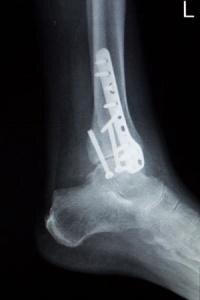

Чаще всего в диагностике перелома голеностопа, как и при любом другом переломе, используется рентгенография. Исследование должно быть выполнено в двух проекциях: в боковой и фронтальной. В качестве дополнительного метода используют компьютерную томографию, чтобы визуализировать ткани сустава в 3D.

Для лечения перелома голеностопа применяются консервативные и оперативные методики лечения. Оперативным методом лечения в настоящий момент пользуются практически все врачи. Огромное значение во время лечения перелома голеностопного сустава имеет грамотно проведенная репозиция костей.

Наиболее точно сопоставить все обломки кости удается только во время операции. А верный выбор фиксатора-импланта поможет костям правильно срастись.